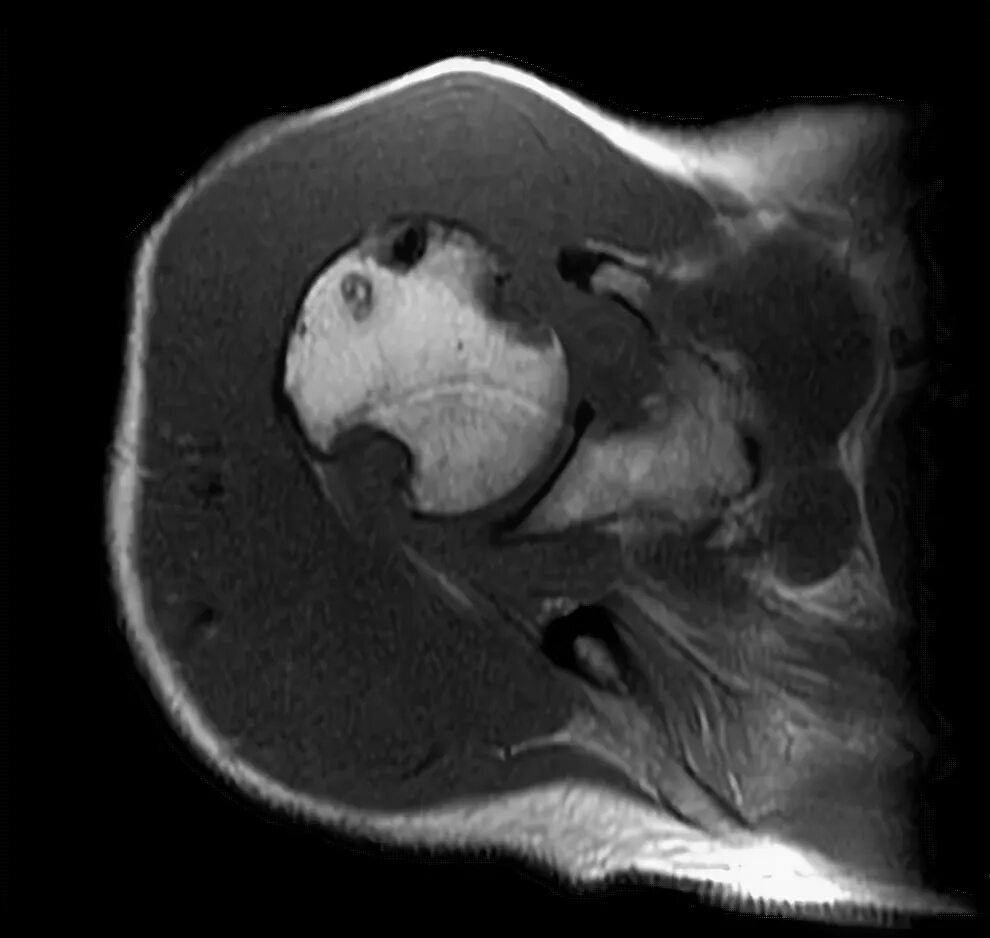

Пигментный виллонодулярный синовит